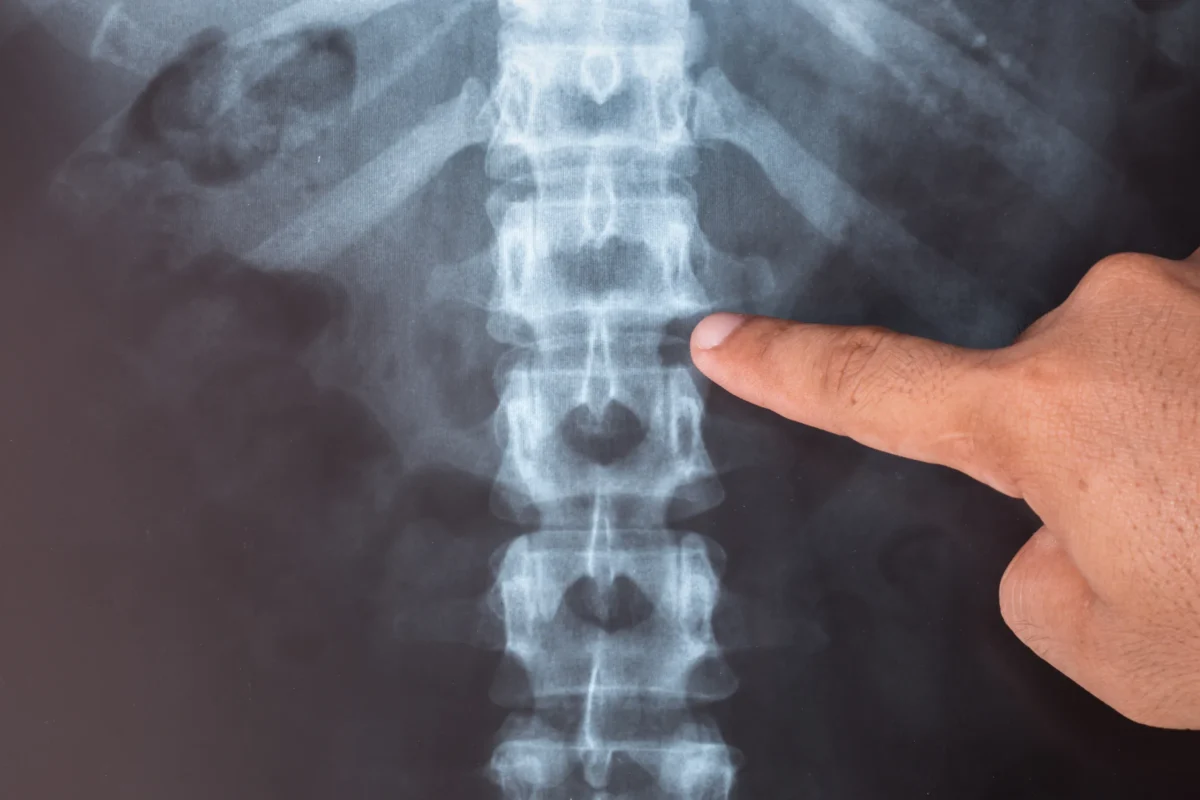

Aplikáciu BMAC vykonáva špecialista v odbore regeneratívnej medicíny. Procedúra prebieha na našom pracovisku pod precíznou navigovanou kontrolou so špičkovými zobrazovacími prístrojmi – RTG s C-ramenom alebo 7StarScope. Koncentrát BMAC sa aplikuje priamo do postihnutej štruktúry alebo zdroja bolesti – napríklad medzistavcovej platničky, kolenného alebo bedrového kĺbu – kde sa môžu naplno rozvinúť jeho regeneračné účinky. Táto aplikačná presnosť výrazne zvyšuje efektivitu zákroku a zároveň minimalizuje riziko komplikácií.

Získaný koncentrát sa aplikuje pod presnou navigáciou RTG prístroja s C-ramenom alebo 7StarScope špeciálnou ihlou priamo do postihnutej štruktúry.